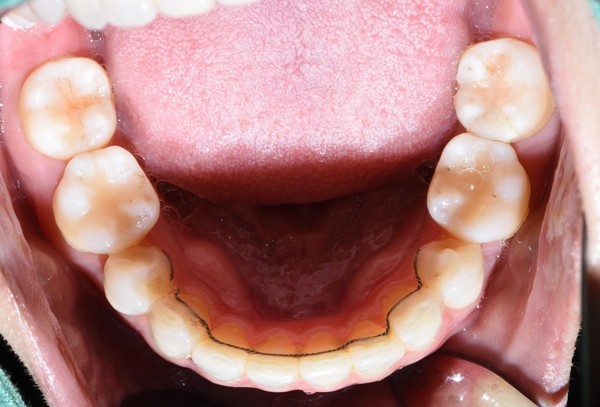

이렇게 말이죠. 위 사진의 환자분의 아래쪽 치아입니다.

다른 치과에서 교정이 끝나고 아래쪽만 유지장치를 붙이고 위쪽은 안붙이셨나봐요.

요렇게 티끌장치를 붙였고, 2주만에 이렇게 변화하셨습니다.

치아의 배열이 달라진게 느껴지시나요?

요렇게 마무리 되었습니다.

물론 안쪽에는 다시 틀어지지 않기 위해 유지장치 부착되어있습니다.